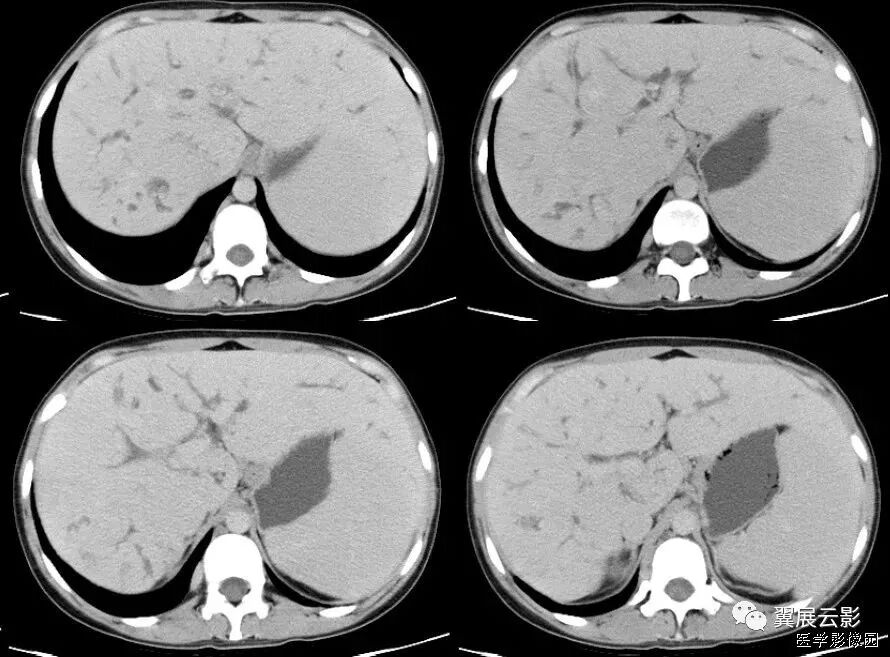

以下两例均是胆管癌,可以看出有明显的肝包膜内陷:

25、肝包膜凹陷征(肝包膜退缩征)

腹部CT扫描时,位于肝脏表面的恶性肿瘤,肝包膜内陷,失去原有的弧度,并与其相续的肝包膜构成一个完整的大弧度,谓之肝包膜凹陷征。

肝恶性肿瘤的发展过程中,小血管,小胆管阻塞引起局限性肝萎缩,肿瘤中央坏死、瘤周纤维组织增生并侵犯肝包膜等多种因素,致使肝包膜向肝内方向收缩,共同导致包膜凹陷征。

虽然肝包膜凹陷征在肝脏恶性肿瘤中出现率并不高,但邻近肝脏肿块的肝包膜凹陷征在许多种恶性肿瘤中都可以出现,包括肝细胞性肝癌、纤维板层性肝、肝内胆管细胞癌、肝转移瘸(原发肿增多为结肠癌、乳腺癌、类癌、肺癌、胆囊癌、胃癌、胰腺癌等)。其病理基础是瘤体中心由于代谢旺盛,血供相对不足,易发生坏死囊变,邻近肝表面的病灶坏死后埸陷,牵拉被膜进而形成脐样凹征。国外学者有认为肝包膜凹陷的机制是由于肿瘤内存在着纤维细胞,尤其肿瘤坏死区纤维细胞增生活跃,当肿瘤细胞侵犯肝包膜后,纤维细胞小均匀的收缩和牵拉,从而可产生肝包膜向内侧方的凹陷。

根据影像学特点将肝包膜凹陷征分成两型:

Ⅰ型,肝包膜凹陷征范围较小,呈反弓状或脐凹状,表面光滑,肝包膜无增厚,凹陷区少有腹腔积液;

Ⅱ型,肝包膜凹陷征范围较广,呈凹坑底状,表面欠光整,肝包膜常不规则增厚,凹陷区多伴腹腔积液。

据文献报道,除巨大肝脏血管瘤偶尔出现肝包膜凹陷征外,良性肿瘤一般不会出现此征,这是由于良性肿瘤一般不存在这种病理改变,所以此征象对肝脏恶性肿瘤的诊断具有特异性,但对鉴别恶性肿瘤的细胞来源并无特异性。此外,肝包膜附近的肝脏炎性病变,尤其是肝脓肿也可出现肝包膜表面凹陷征;同时要注意与肝硬化进行鉴别诊断,典型肝硬化肝表面凹凸不平,呈波浪状或驼峰状,肝包膜凹陷多发且较表浅,CT平扫再生结节可呈多发等密度或高密度影,但增强扫描门脉期和延迟期结节影呈等密度,使凹陷区与邻近肝实质密度基本一致。